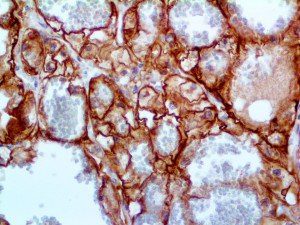

It is the ICU physician who is most likely to witness one of the deadliest manifestations of the abnormal immunological response, the cytokine storm syndrome (CSS). This response is also referred to by some as the cytokine release syndrome (CRS). CSS is characterized by continuous activation and expansion of macrophage and lymphocyte populations, which secrete large amounts of cytokines, causing the cytokine storm. This massive cytokine release is akin to hemophagocytic lymphohistiocytosis (HLH) disease, a syndrome characterized by initial unchecked and persistent activation of cytotoxic T lymphocytes and NK cells.

Clinical and laboratory manifestations of HLH include fever, enlarged liver and/or spleen, neurologic dysfunction, coagulopathy, liver dysfunction, cytopenias (i.e., low levels of erythrocytes, leukocytes, and/or platelets), hypertriglyceridemia, hyperferritinemia, hemophagocytosis, and eventually diminished NK cell activity as the immune system becomes progressively paralyzed. HLH can be familial (primary HLH) or secondary to another disease process (sHLH), such as rheumatic disease, in which it is referred to as macrophage activation syndrome (MAS, characterized by elevated ferritin).

This activation induces inflammatory monocytes to highly express IL-6, starting a localized and then systemic cascade effect that results in hyperproduction of IL-6, which accelerates the inflammatory process. Because IL-6 also increases vascular permeability, excessive levels cause blood vessels to become very leaky. This, along with clotting factors released from vascular endothelial cells, stimulates the coagulation cascade, resulting in microthrombosis (tiny clots), which leads to ischemia and tissue death of the kidney, intestines, heart, liver, brain and extremities.